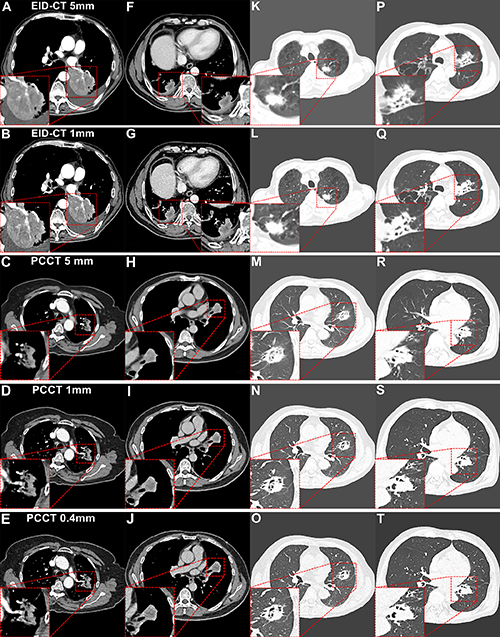

Figure 4. Contrast-enhanced chest CT images of lung cancer from energy-integrating detector (EID) CT and photon-counting CT (PCCT). The red outlined areas highlight the magnified images of lesions. (A–E) Vessel convergence or invasion sign in the axial images of the arterial phase. (A, B) EID CT images in a 74-year-old man with a body mass index (BMI) of 18.6, calculated as weight in kilograms divided by height in meters squared, diagnosed with adenocarcinoma. (C–E) PCCT images in a 72-year-old woman (BMI, 20.0) diagnosed with adenocarcinoma. The vessels’ delineation and continuity are more distinct in PCCT 0.4-mm images. (F–J) The boundary of the necrotic area within the tumor in the axial images of the venous phase. (F, G) EID CT images in a 62-year-old man (BMI, 23.8) diagnosed with squamous cell carcinoma. (H–J) PCCT images in a 60-year-old man (BMI, 23.6) diagnosed with squamous cell carcinoma. The improved spatial resolution and iodine signal of PCCT enhance the delineation of the necrotic area boundary within the tumor, particularly in the 0.4-mm images. (K–O) Lobulation, spiculation, and pleural retraction in the axial images with lung windows. (K, L) EID CT images in an 82-year-old man (BMI, 20.8) diagnosed with adenocarcinoma. (M–O) PCCT images in a 72-year-old man (BMI, 23.5) diagnosed with adenocarcinoma. Compared with EID CT and other section thicknesses, PCCT at 0.4 mm demonstrates better diagnostic confidence for subtle spiculations, shallow lobulations, and pleural traction lines. (P–T) Bronchial stenosis or cutoff sign in the axial images with lung windows. (P, Q) EID CT images in a 70-year-old man (BMI, 20.5) diagnosed with squamous cell carcinoma. (R–T) PCCT images in a 58-year-old man (BMI, 21.8) diagnosed with squamous cell carcinoma. PCCT at 0.4 mm improves the visualization of stenosis, truncation, and their boundary morphology relative to EID CT.